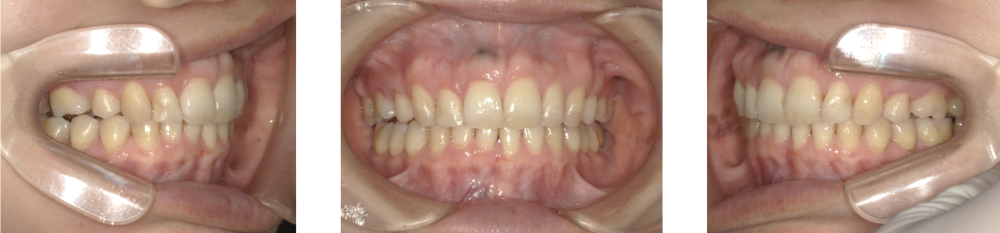

Before Photo

Before

After Photo

After

主訴

出っ歯が気になる。

治療期間

3年5か月

料金

相談料0円、検査料33,000円、動的矯正治療費990,000円、保定装置料5,500円x5枚(必要枚数)

治療概要

出っ歯の原因が下顎の位置が後方に偏位していることと上の前歯が突出していることであった。

治療方針としては下顎の前方誘導及び、上顎小臼歯を抜歯して上顎前歯を後退させた。

矯正での歯の移動のリスクとして歯根吸収、歯肉退縮、歯髄怪死が考えられます。

保定装置の装置を怠ると隙間が生じてくる可能性があります。